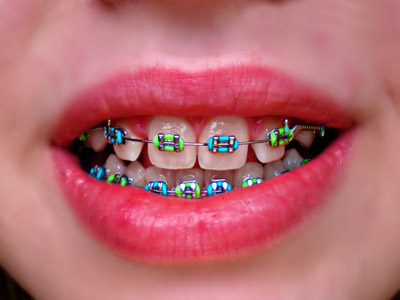

ارتودنسی